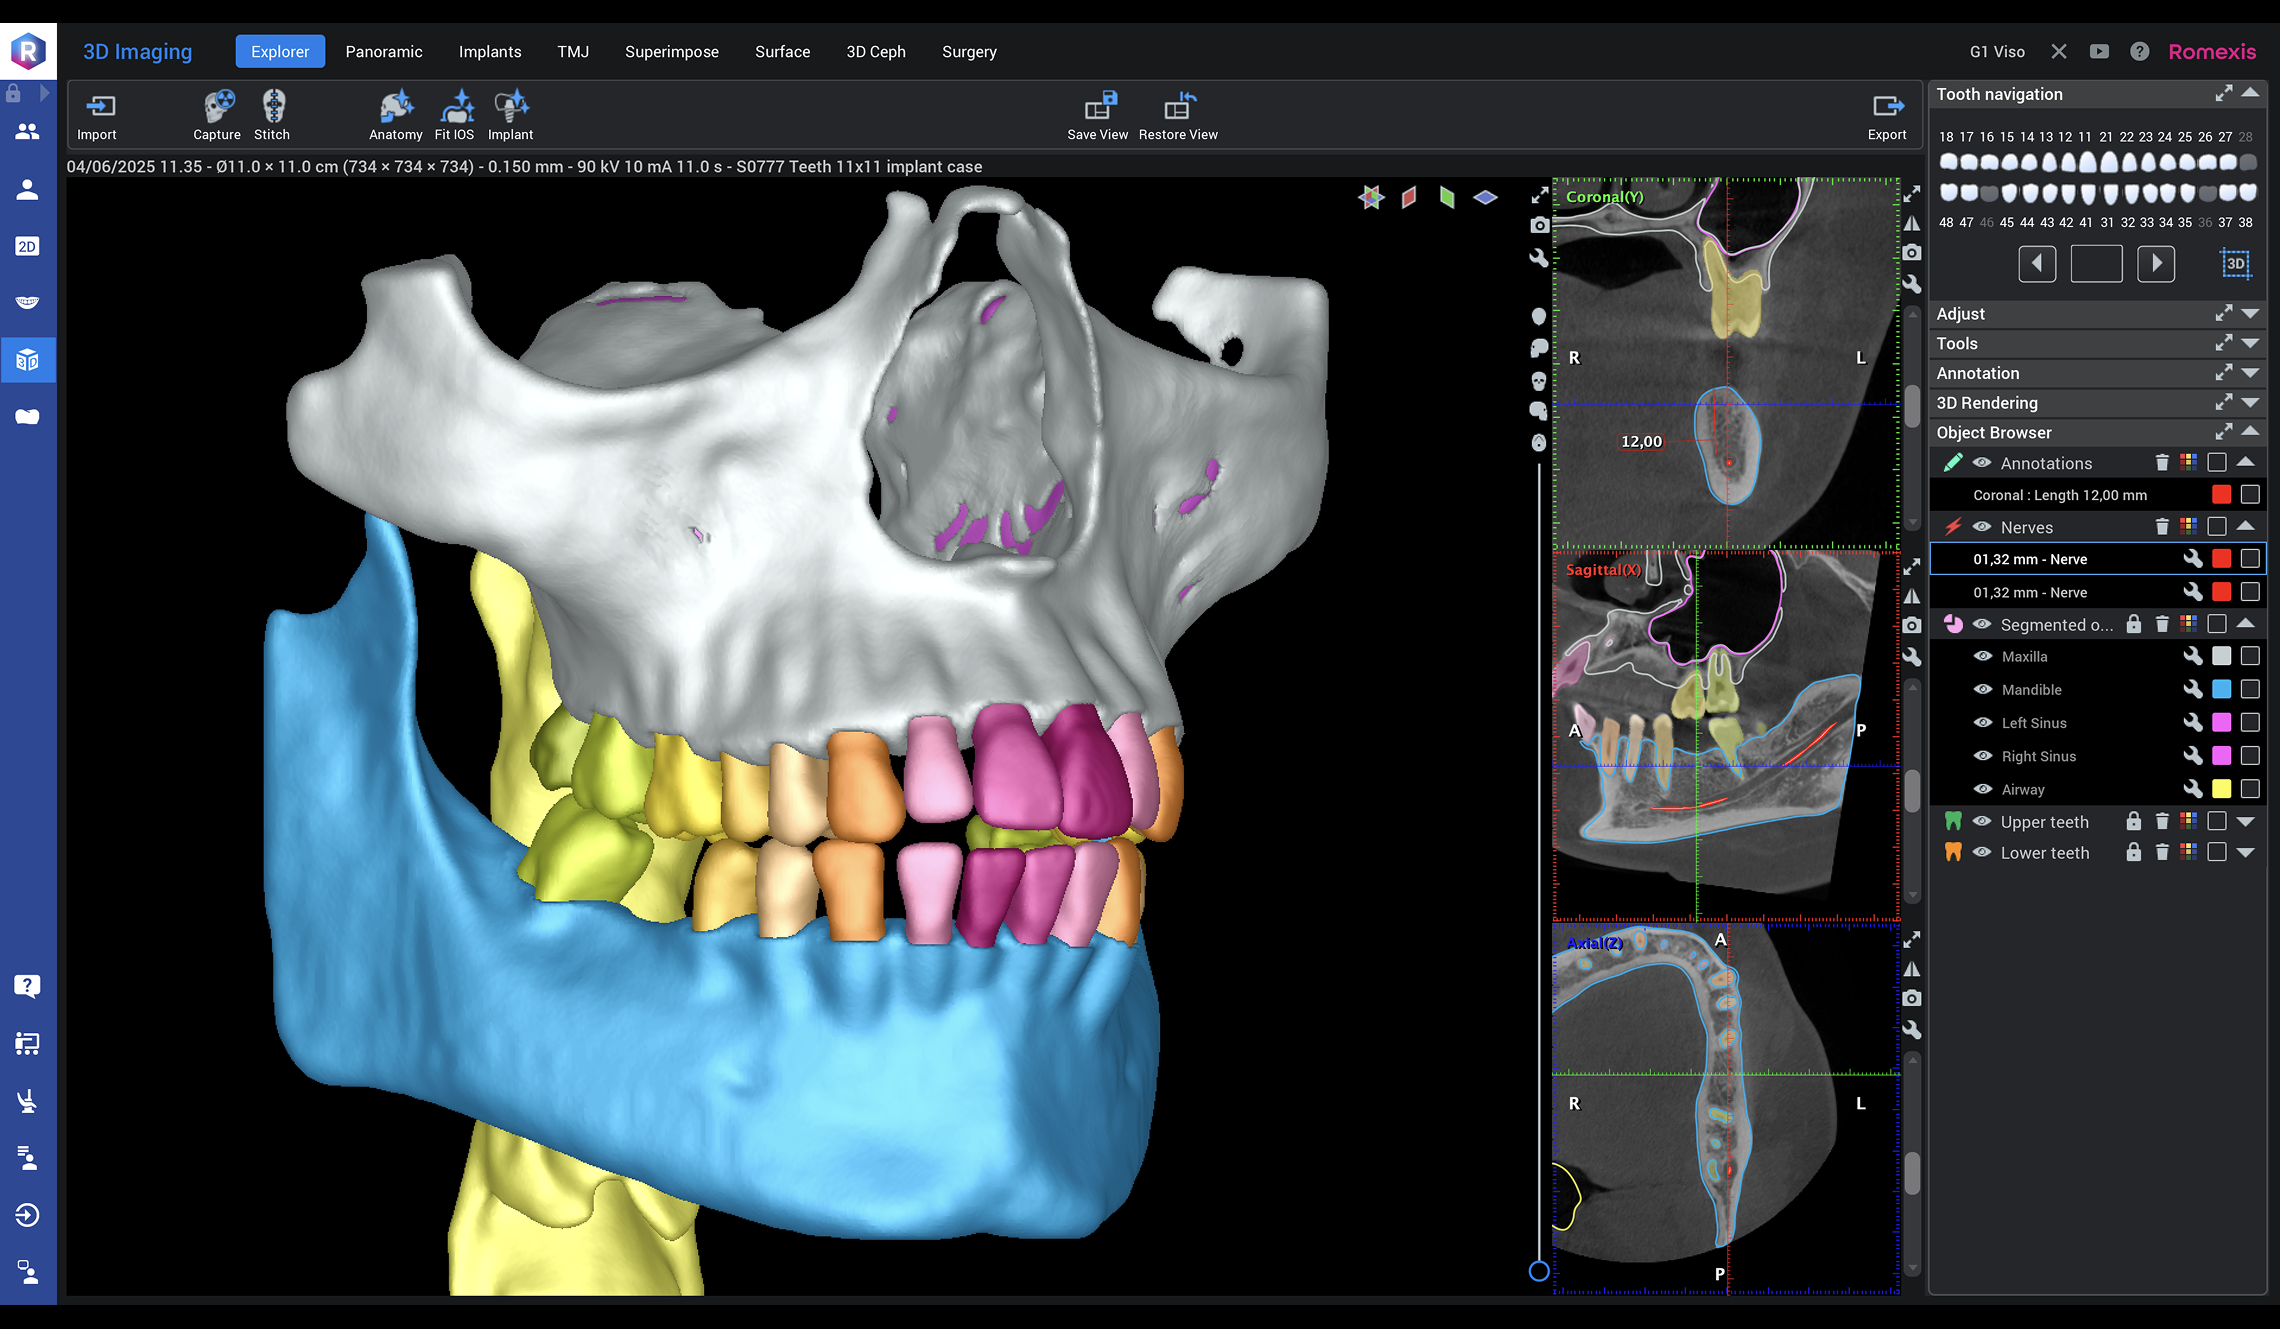

Viso G1

A powerhouse dental CBCT imaging unit covering volume sizes up to 11 x 11 cm.

With top-of-the-line 3D imaging technology and all the essential dental imaging programs, Planmeca Viso G1 is an X-ray device which easily meets every day dental imaging demands.

Why choose Planmeca Viso®? Planmeca Romexis®